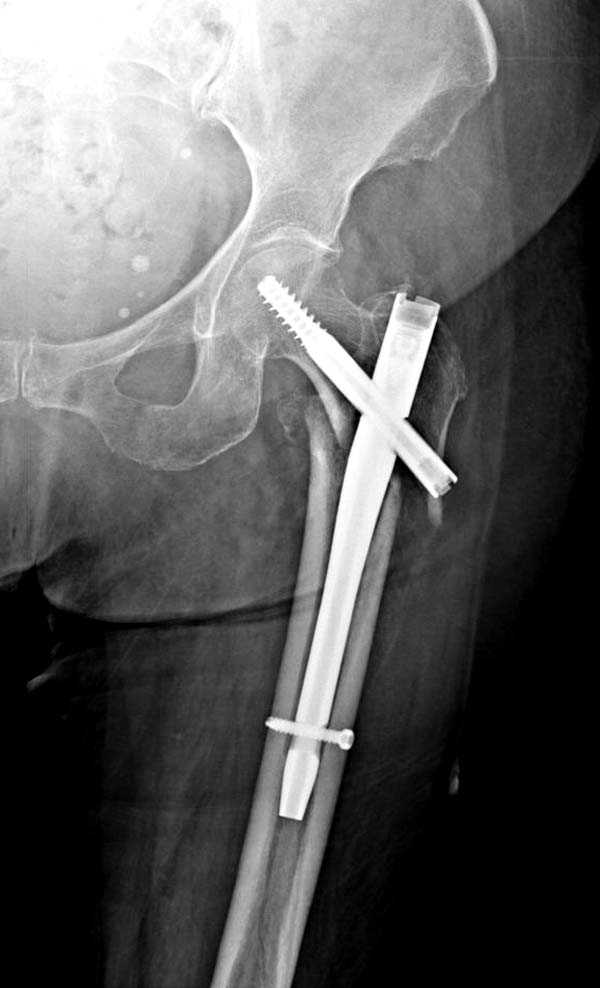

При первом послеоперационном поликлиническом осмотре больная предъявила жалобы на боли в бедре. В серийных снимках обнаружен продольный перелом верхнего отдела бедра.

Считаем, что техническая ошибка произошла во время установки гвоздя, когда рассверливанию канала не уделили должного внимания. Канал остался узковат, и гвоздь был забит с силой. Полная нагрузка конечности приостановлена на две недели, и боли в конечности изчезли. Больная начала нагрузку и перелом срастается.-- Djoldas Kuldjanov, M.D.Associate ProfessorDepartment of Orthopedic SurgerySt. Louis University

Мне тоже представляется, что это не единственная проблема. Продольные трещины заживают легко и быстро. Интересно, почему увеличился варус и

появилась медиализация дистального отломка.

Мне думается, что варусное положение проксимального отломка на последующих снимках не более чем проекционный феномен. Раскол же диафиза вдоль, наверняка, связан с чрезмерно насильственным введением штифта. Вообще, при реверсивных, да и обычных вертельных переломах, многие давно отказались от короткой Гаммы в пользу long-версии. Но в любом случае надо быть на 100 уверенным в подготовке канала.